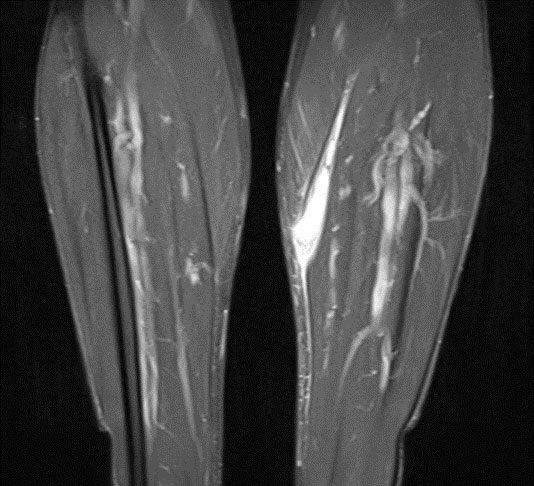

On clinical examination, the patient reported significant pain of the muscle on stretching and pressure. Distal perfusion, motor function and sensory function were normal. One week after the MRI examination, the first follow-up ultrasound scan was obtained. No continuous pennate appearance of the medial head of the gastrocnemius was evident, only mild residual seroma, while elastography was unremarkable. Further ultrasound scans were obtained every seven days to monitor progress (Figs. 3 – 5). At each review appointment, the temperature on the contralateral side was also measured (Delta T), and the visual analogue scale (VAS) was recorded to quantify the pain.